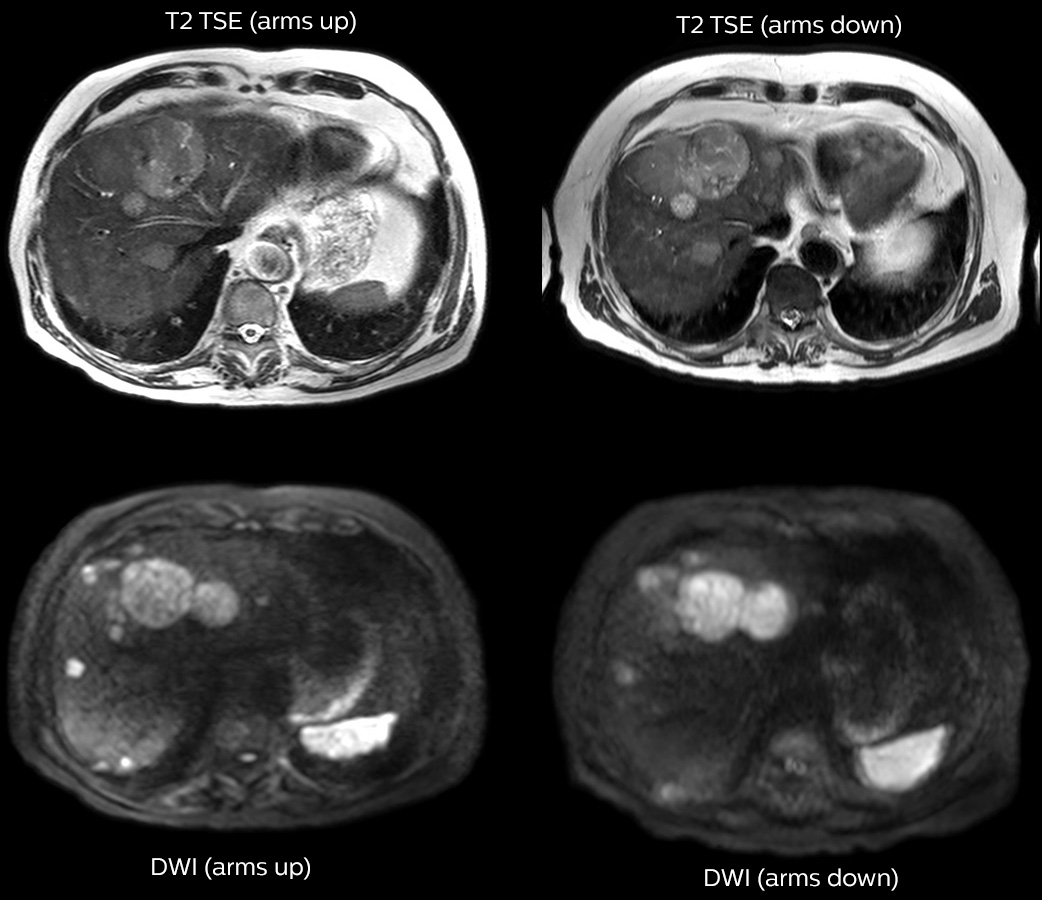

Dr. Kukuk scans an increasing number of liver patients in an arms-up position using the integrated Posterior coil and a special positioning device. “By placing the patient’s arms up, the field of view in the right-left direction can be smaller so that a right-left preparation direction can be used to cut down the scan time,” he explains. “We can use high dS SENSE factors for TSE imaging, so we can shorten the echo train length. This results in a faster scan than arms-down T2 TSE and the images show high anatomical detail.”

“For DWI, the high dS SENSE factor allows using a shorter TE so we get higher signal and fewer susceptibility artifacts, which means less distortion of diffusion weighted images. Of course, with higher dS SENSE factors and the shortening of the TSE factor in T2-weighted imaging, we can drastically cut down the complete examination time. So, with arms-up we get faster images, less distortion in DWI and less blurring on T2-weighted images. Almost all patients tolerate the arms-up scanning well.”